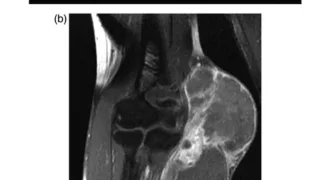

大腿骨頚部骨折の闘病日記 手術日+581日目 2025/10/1(水)(ひじの軟部肉腫)